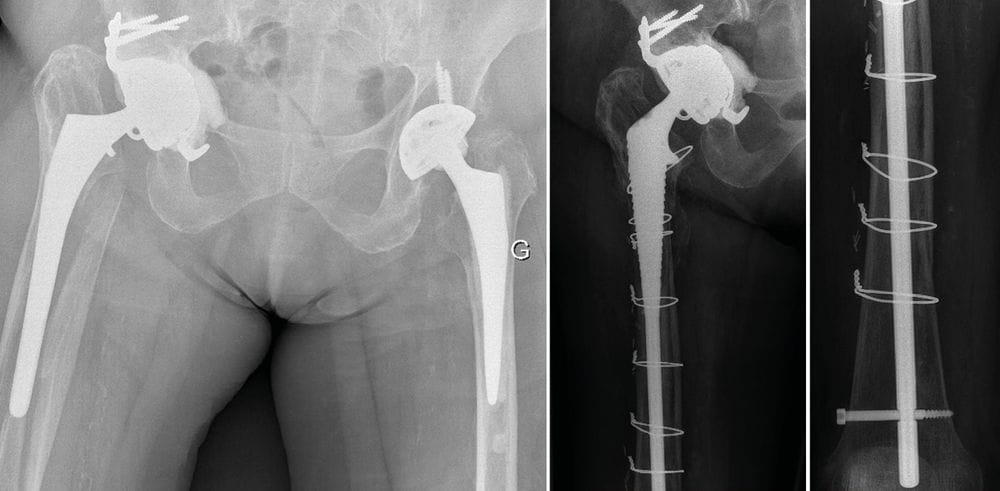

Case report n°3

Female aged 65 at the consultationHistory of the illness:

- 1973: Fractured acetabulum. Fracture repair

- 1975: THA, complicated by dislocations

- 2000: First revision (R1) in 2 stages due to chronic infection: Kerboull cross-plate + cemented stem (Figure 3)

Clinical examination:

- Groin pain

- Unable to weight-bear

- -8 cm

Case report n°4 (Figure 4)

- Paprosky stage 3A acetabular loosening

- Charnley monoblock femoral stem

- Femoral osteolysis in zone 6–7

Case report n°5 (Figure 5)

- Two-stage two component revision.

- 1 year post-surgery (Figure 6)

- LLD -5 cm

- Walks with a stick

- Slight limp TDB

- MF 3/5